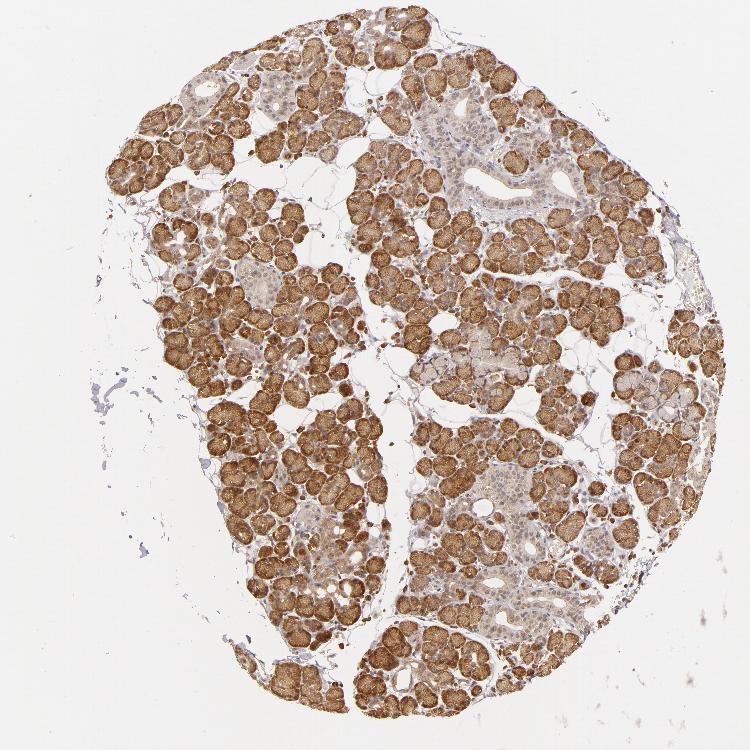

SALIVARY GLAND - Antibody stainingi

Antibody staining in the annotated cell types in the current human tissue is reported as not detected, low, medium, or high, based on conventional immunohistochemistry profiling in selected tissues. This score is based on the combination of the staining intensity and fraction of stained cells.

Each image is clickable and will lead to virtual microscopy that enables deeper exploration of all samples and also displays staining intensity scores, fraction scores and subcellular localization as well as patient and tissue information for each sample.

Antibody HPA003995Antibody HPA005700Antibody HPA030069Antibody CAB002683

Glandular cells MediumMediumMediumMedium